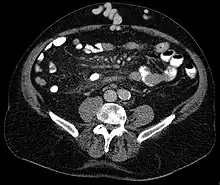

Axial CT showing portosystemic collateral circulation via the umbilical vein: caput medusae in liver cirrhosis

Caput medusae is the appearance of distended and engorged superficial epigastric veins, which are seen radiating from the umbilicus across the abdomen. The name caput medusae (Latin for "head of Medusa") originates from the apparent similarity to Medusa's head, which had venomous snakes in place of hair. It is also a sign of portal hypertension.[1] When the portal vein, that transfers the blood from the gastrointestinal tract to the liver, is blocked, the blood volume increases in the peripheral blood vessels making them appear engorged.[2] It is caused by dilation of the paraumbilical veins, which carry oxygenated blood from mother to fetus in utero and normally close within one week of birth, becoming re-canalised due to portal hypertension caused by formation of scar tissue (fibrosis) in liver.The appearance is due to cutanous portosystemic collateral formation between distended and engorged paraumbilical veins that radiate from the umbilicus across the abdomen to join systemic veins.[3]

In Liver Cirrhosis, the paraumbilical veins open up to transfer portal venous blood into systemic circulation. It results in caput medusae.[5]